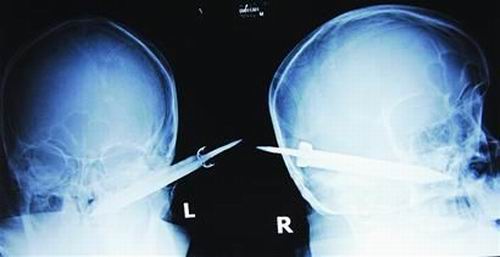

經(jīng)過(guò)檢查,醫(yī)生說(shuō)這把長(zhǎng)有10厘米左右的刀,從右耳窩上前方直接刺進(jìn)了鼻腔,離頜內(nèi)大動(dòng)脈很近,刀卡在了骨頭中,要取出這把刀最怕大出血,萬(wàn)幸的是這把三棱刀并沒(méi)有傷及大腦。

截至昨晚11時(shí)30分,患者頭部刀經(jīng)手術(shù)已取出,生命體征平穩(wěn)。(芮瀟瀟)